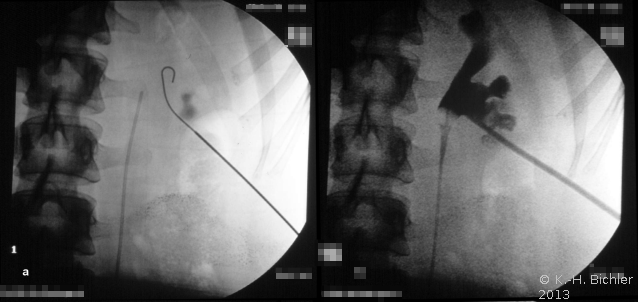

Bei der perkutanen Litholapaxie wird ausgehend von einer zumeist sonographiegesteuerten Punktion des Nierenhohlraumsystems und Dilatation des Punktionskanals ein Pyeloskop zur Steinzertrümmerung bzw. Entfernung eingeführt (Abbildung 7).

Bei der Anwendung perkutaner Methoden im Kindesalter ist die Größe des Instruments von Bedeutung. Hier hat sich ein miniaturisiertes Pyeloskop bewährt:

Mini-PERC der Firma Wolf